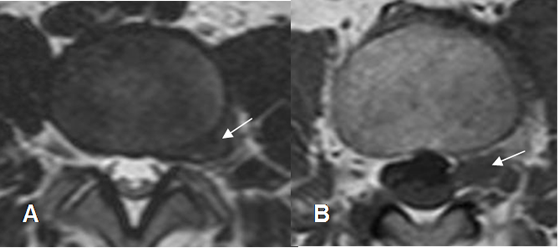

Fig 99. Hernia paramediana.

A y B: TAC axial. Imágenes con densidad de tejidos blandos que ocupan el receso lateral, comprimen las raíces nerviosas y corresponden a hernias paramedianas.

Fig 100. Hernia paramediana.

A y B: RM axial en T2. Imágenes con densidad de tejidos blandos que ocupan el receso lateral, comprimen las raíces nerviosas y corresponden a hernias paramedianas.